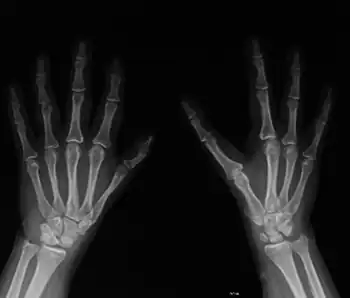

Diamond–Blackfan anemia is characterized by normocytic or macrocytic anemia (low red blood cell counts) with decreased erythroid progenitor cells in the bone marrow. This usually develops during the neonatal period. About 47% of affected individuals also have a variety of congenital abnormalities, including craniofacial malformations, thumb or upper limb abnormalities, cardiac defects, urogenital malformations, and cleft palate.[4] Low birth weight and generalized growth delay are sometimes observed. DBA patients have a modest risk of developing leukemia and other malignancies.